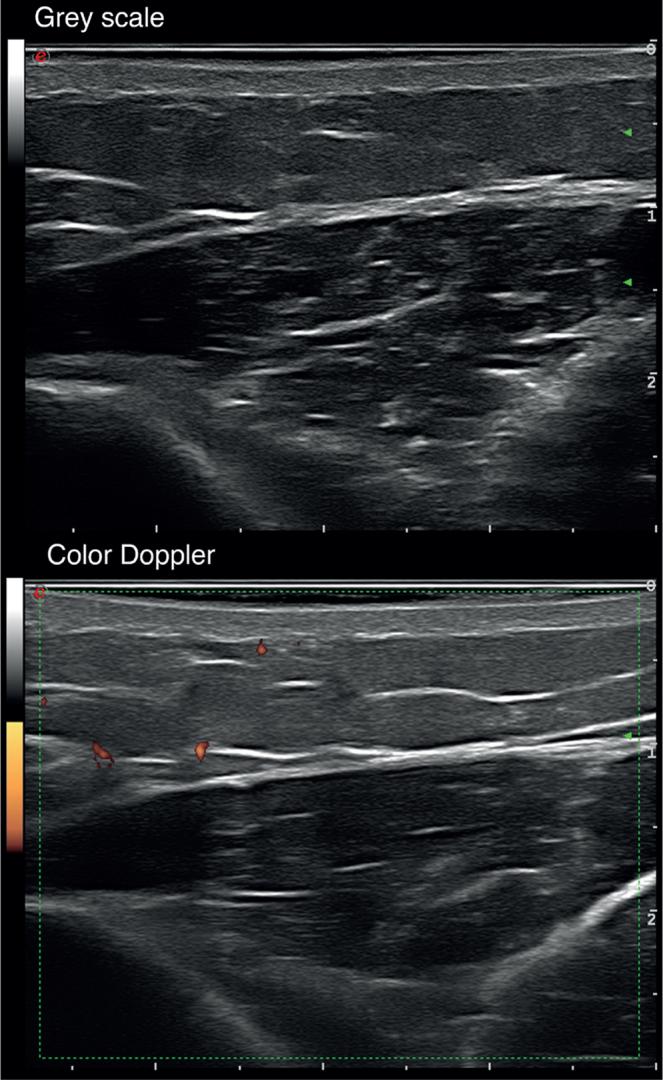

Sclerodermoid chronic graft-versus-host disease (scGVHD) is a severe complication of allogeneic haema-- topoietic stem cell transplantation. The aim of this study was to investigate the usefulness of high-frequency ultrasound of the skin in assessing the inflammatory patterns and prognosis of patients with scGVHD. A prospective study was carried out with patients who developed scGVHD in the period June 2016 to April 2018. Clinical and ultrasound examinations were performed on the first visit and at 6-month follow-up. A total of 24 patients were included in the study. A 6-month follow-up high-frequency ultrasound of the skin was performed on 20 of the 24 patients. Abnormal B-mode findings in high-frequency ultrasound of the skin consisted of hypoechogenic dermis, hypoechogenicity of septa and hyperechogenicity of lobules in hypodermis. No differences were observed in these basal parameters between treatment progressive/non-responding and inactive/responding scGVHD groups of patients. Basal Doppler showing increased vascular flow with a systolic peak ≥10 cm/s and a vascular resistance index ≥ 0.70 was observed only in those patients who developed progressive/non-responding scGVHD (62.5% vs 0% p = 0.006). In conclusion, Doppler ultrasound is a useful tool to assess the inflammatory activity and outcome of scGVHD. These findings could enhance patient management and help to guide treatment decisions.

硬皮病样慢性移植物抗宿主病(scGVHD)是异基因造血干细胞移植的一种严重并发症。本研究的目的是探讨皮肤高频超声在评估scGVHD患者炎症模式和预后方面的作用。对2016年6月至2018年4月期间发生scGVHD的患者进行了一项前瞻性研究。在首次就诊时和6个月随访时进行临床和超声检查。共有24例患者纳入研究。24例患者中的20例进行了6个月随访的皮肤高频超声检查。皮肤高频超声的异常B超表现包括真皮低回声、间隔低回声和皮下小叶高回声。在治疗进展/无反应组和无活动/有反应组的scGVHD患者之间,这些基础参数未观察到差异。仅在发生进展/无反应性scGVHD的患者中观察到基础多普勒显示血管血流增加,收缩期峰值≥10 cm/s,血管阻力指数≥0.70(62.5%对0%,p = 0.006)。总之,多普勒超声是评估scGVHD炎症活动和预后的有用工具。这些发现可加强患者管理并有助于指导治疗决策。